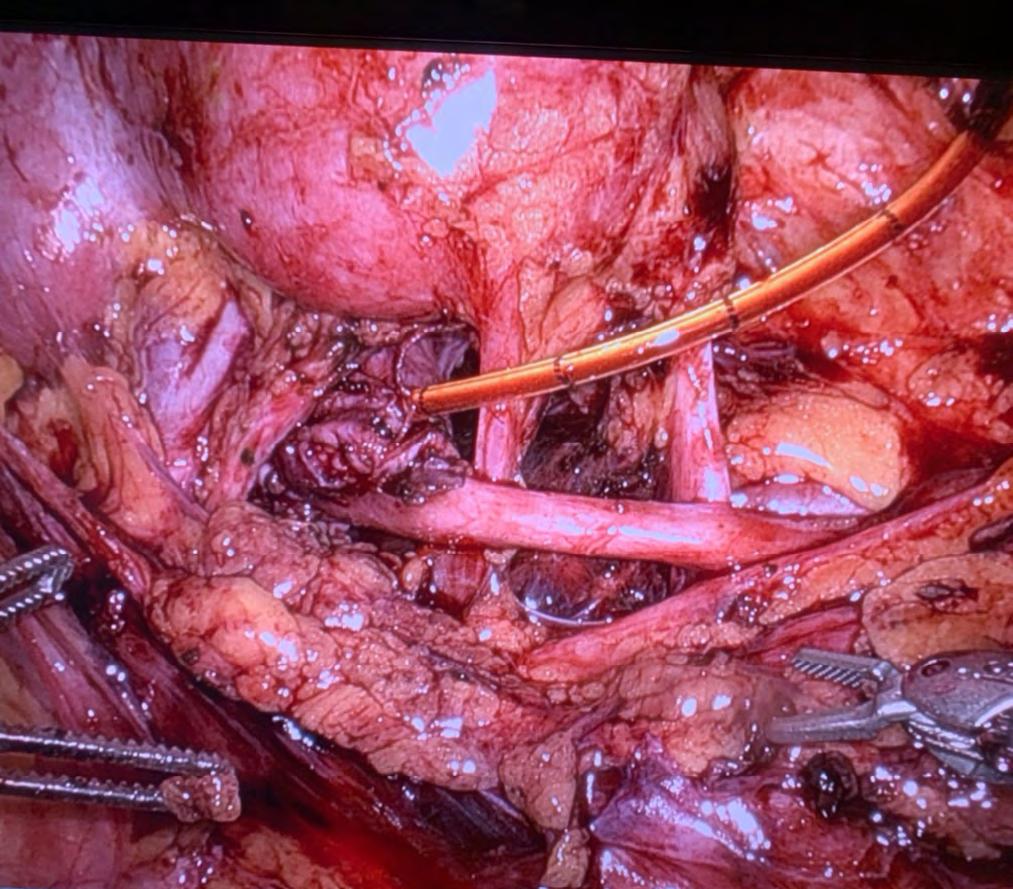

Souhrn: Cíl: Verifikace efektivity ischemie ledviny při klampování renální arterie při miniinvazivní resekci tumoru ledviny je možná, dle vzhledu ledviny, pomocí dopplerovské ultrasonografie a pomocí podání indocyaninové zeleně (ICG – indocyanine green) s aplikací úzkého světelného spektra – NIR (near infrared) zobrazení/fluorescence. U většiny případů si vystačíme s prvními dvěma metodami, ICG užíváme velmi limitovaně jen při selektování klampování mnohočetných tepen či větví renální tepny. Video ukazuje využití ICG při robotické resekci (RR) tumoru ledviny při duplexní renální arterii. Soubor: Technologii ICG s NIR zobrazením máme k dispozici od července 2018. V období od července 2018 do května 2020 byla použita u 19 (15,2 %) ze 125 laparoskopických resekcí – vybavení Olympus Visera Elite CLV-S200-IR. U RR byla využita v období od června 2020 do října 2025 u 9 (2,4 %) z 340 případů. Při RR užíváme technologii FireFly™ systému da Vinci Xi. Technika: Po zaklampování renální arterie (většinou selektivní klampování jen některé z větví) je intravenózně aplikováno 1,25 mg ICG (Verdye®) a zobrazení je přepnuto z klasického módu do fluorescenčního zobrazení NIR (FireFly™). Video zobrazuje popsanou metodiku při selektivním klampování duplexní renální arterie při RR. Výsledky: U všech 28 případů metodika jasně zobrazila ischemickou část ledviny. Závěr: K verifikaci efektivity ischemie při klampování renální arterie či jejích větví užíváme většinou dopplerovské zobrazení. Ve vysoce selektovaných případech (zejména mnohočetné tepny či klampování jen větve arterie) je možno využít podání ICG s NIR zobrazením. Klíčová slova: tumor ledviny – resekce – laparoskopie – robot – ICG

Summary: Objective: Verification of renal ischemia during renal artery clamping in minimally invasive renal tumor resection is possible based on the appearance of the kidney, using Doppler ultrasonography and indocyanine green (ICG) administration with narrow light spectrum application (NIR (near infrared) imaging/fluorescence). In most cases, the first two methods are sufficient; we use ICG very sparingly, only when selecting clamping of multiple arteries or branches of the renal artery. The video shows the use of ICG in robotic resection (RR) of a kidney tumor with a duplex renal artery. Abstract: ICG with NIR imaging technology has been available since July 2018. Between July 2018 and May 2020, it was used in 19 (15.2%) of 125 laparoscopic resections – Olympus Visera Elite CLV-S200-IR equipment. For RR, it was used in 9 (2.4%) out of 340 cases between June 2020 and October 2025. For RR, we use the

FireFly™ technology of the da Vinci Xi system. Technique: After clamping the renal artery (usually selective clamping of only some of the branches), 1.25 mg of ICG (Verdye®) is administered intravenously and the display is switched from classic mode to NIR fluorescence imaging (FireFly™). The video shows the described methodology for selective clamping of the duplex renal artery during RR. Results: In all 28 cases, the methodology clearly showed the ischemic part of the kidney. Conclusion: We usually use Doppler imaging to verify the effectiveness of ischemia during clamping of the renal artery or its branches. In highly selected cases (especially multiple arteries or clamping of only one branch of the artery), ICG administration with NIR imaging can be used.